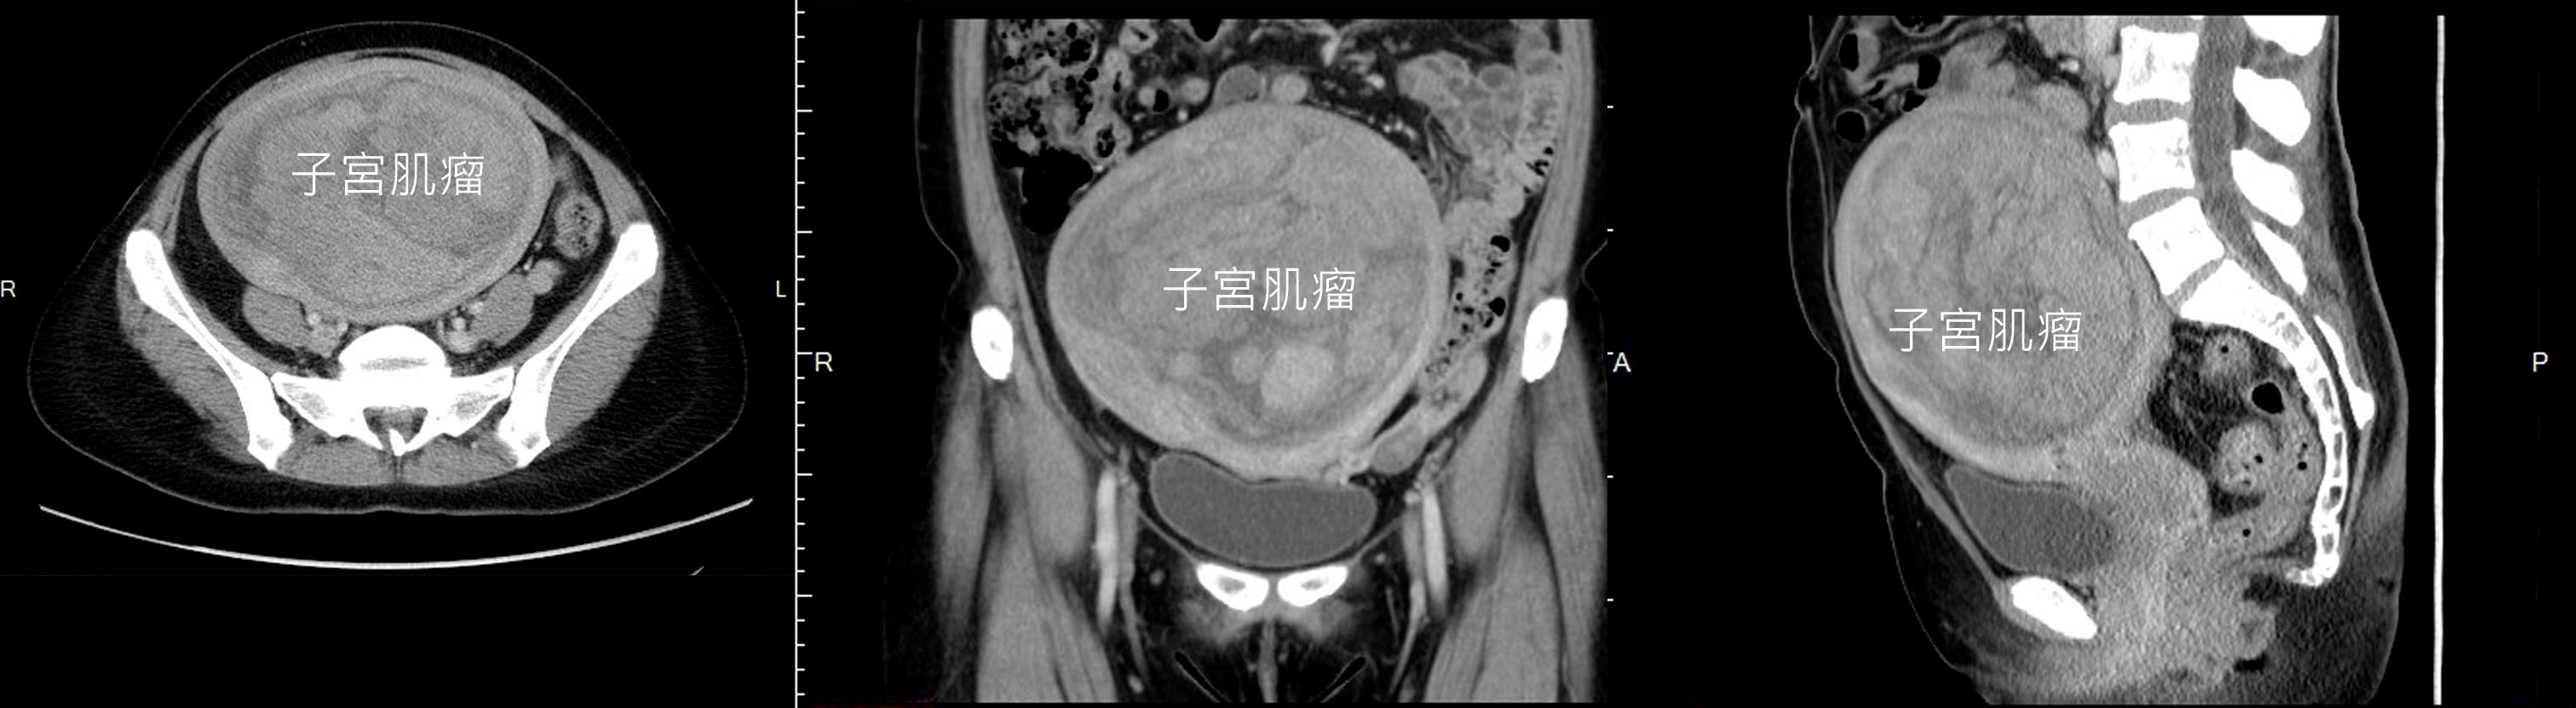

Q5:什麼是子宮肌瘤以及症狀珄

A5:子宮肌瘤是在骨盆腔中,最常見的良性腫瘤。子宮肌瘤不會發生在青春前期的女孩,大都發生在生育年齡的婦女中,大約1/4的婦女都有子宮肌瘤,而年紀愈大的婦女,其比例愈高,可以到40-50%的機會。如果將切除下來的子宮做分析,更有8成的子宮內含有子宮肌瘤,如果仔細的切片,有統計發現停經前的婦女平均有7.6個肌瘤;在更年期後,大部分但不是全部,子宮肌瘤會萎縮。但是很幸運的,這些長在子宮上的肌瘤大多是良性,停經前惡性的比例大約只有0.2%;但是如果停經後肌瘤還是持續長大且合併不正常出血和腹痛,其惡性的機會就會上升到1%,因此如果有子宮肌瘤的婦女最好停經前後還是要持續追蹤肌瘤的狀況。

子宮肌瘤的症狀

一、不正常子宮出血

這是肌瘤最常見的症狀,特別是肌瘤位置在子宮內膜上的時候,可能會導致經血量過長過多,嚴重的時候會造成貧血。

二、疼痛

肌瘤內部或是有變性或壞死,有時會讓患者覺得十分疼痛,這通常在比較大的肌瘤才會發生。

三、腹部腫塊

比較瘦的人和過大的肌瘤可能會在腹部摸到硬塊,在診斷為肌瘤前,患者常常認為自己變胖。

四、泌尿道症狀

若肌瘤壓迫到膀胱可能會讓膀胱容積變小導致頻尿,壓迫到直腸會造成排便不順。

五、不孕或流產

長在子宮內膜上的肌瘤,可能會讓該處的血行或內膜不穩定,影響胚胎著床;若肌瘤位置剛好在胚胎附近,可能會壓迫阻礙胚胎的發育,造成胎兒畸型或流產。